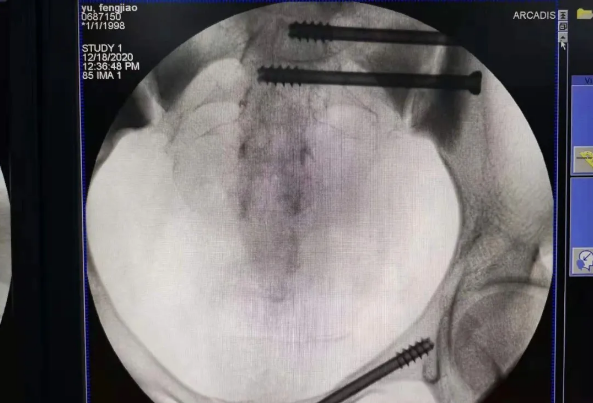

在南昌市第一医院廖琦教授带领下,由创伤骨科团队借助天玑®骨科手术机器人为患者“量身定做”最理想、最安全的教科书般的通道,完美安全微创完成手术,并且手术时间明显缩短,真正做到“指哪儿打哪儿”!更让患者放心的是,天玑®骨科手术机器人的“稳定手”机械臂进行精准定位,不用反复探寻。

由于天玑®骨科手术机器人的精准及高效,可以使手术时间明显缩短,因此在骨盆骨折手术后,在廖琦教授指导下,脊柱外科团队利用天玑®骨科手术机器人同样为20岁女性腰椎骨折患者“量身定做”最理想、最安全的教科书般的通道,完美安全微创完成手术,手术不仅时间缩短,并且出血和透视减少。

天玑®骨科手术机器人系统由机械臂主机、光学跟踪系统、主控台车构成,“透视眼”、“稳定手”是它的厉害之处,因此一举解决了骨科手术有三大难题:视野差、精准难、不稳定。

➁ 机械臂就是天玑®骨科手术机器人的“稳定手”,运动灵活、操作稳定,能达到亚毫米的精度;

➂ 主控电脑系统就等于天玑®骨科手术机器人的大脑,智能传达着医生的想法给以上两个设备,帮助医生进行“路径规划”,术中还能跟踪患者术中的移动,机器人手臂位置自动补偿,保障手术路径与计划路径一致。